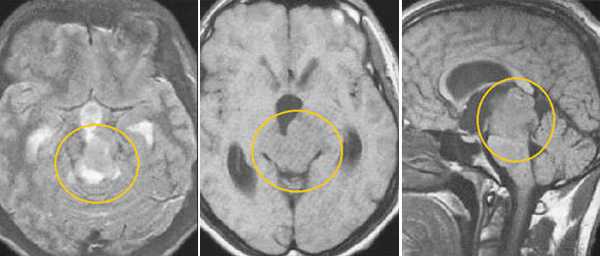

Пинеоцитома. На Т2 ВИ опухоль состоит из двух участков разной интенсивности МР-сигнала: высокой в передних отделах и низкой в задних. Четкость и линейность перехода свидетельствует о кистозном характере строения опухоли. Различия интенсивности МР-сигнала от жидкости в передних и задних отделах опухоли обусловлены эффектом «седиментации» белковых компонентов (вероятнее компонентов крови), опускающихся вниз при положении головы пациента на затылке.

Пинеоцитома. МРТ в режиме Т2 и Т1 выявляется солидного строения опухоль задних отделов III желудочка мозга. На фоне в/в контрастирования определяется выраженный и достаточно гомогенный характер контрастирования опухоли.